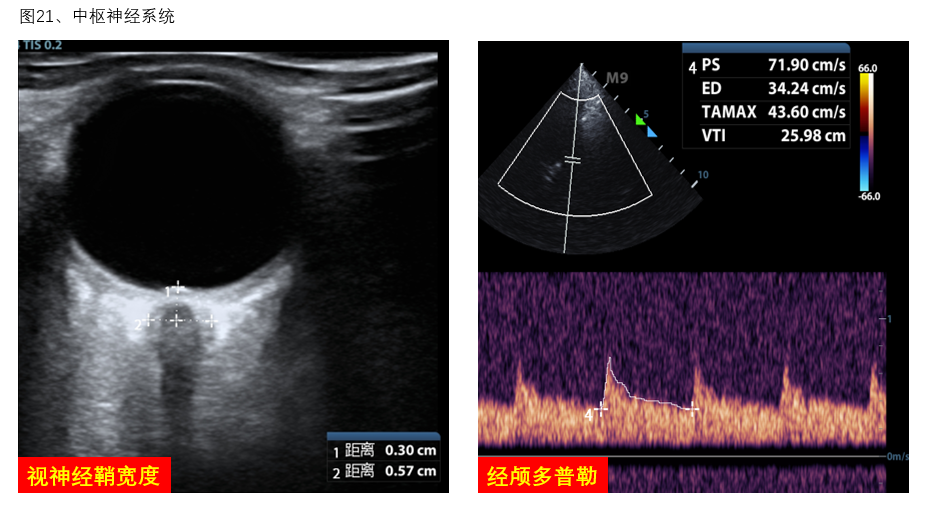

5、中枢神经系统:大脑中动脉血流多普勒可协助评估脑血流灌注,协助调整VA-ECMO流量。视神经鞘宽度的超声探查可协助评估和管理患者脑水肿情况(图21)。

图21 中枢神经系统